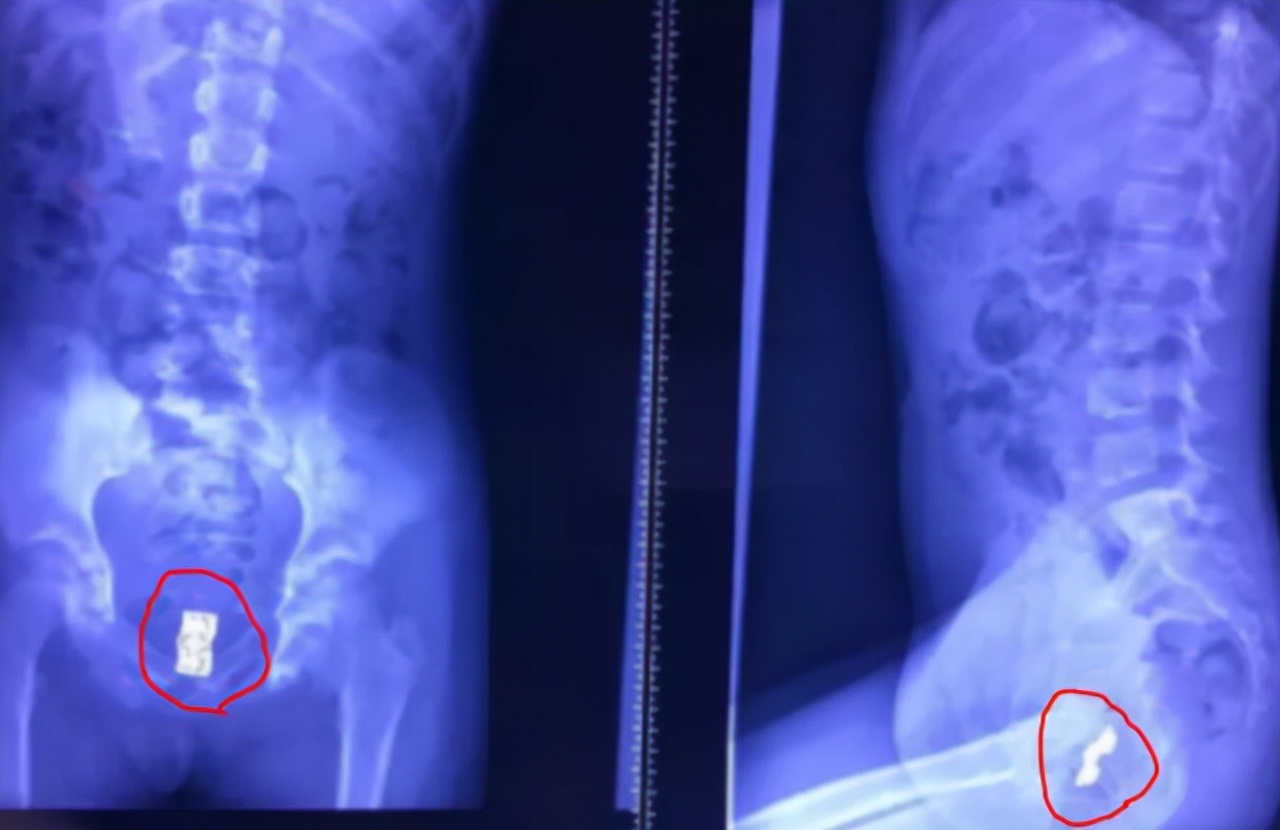

女人仔细检查后发现,这股臭味并不是衣服上的,而是来自女儿身上,检查无果后小两口带着孩子去了医院,经过检查医生从女儿的*体下**取出了很多塑料玩具,一看就是孩子玩具的小零件。

医生表示:这些玩具在孩子体内停留最少半年之久。找到原因后女人和丈夫十分自责,从和女儿聊天中得知,她很早之前就觉得下面不舒服,有时候痒得厉害就会把东西塞进去。